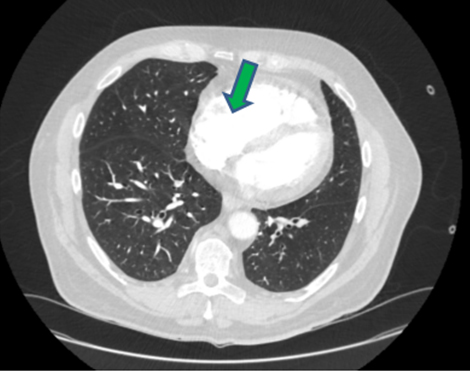

As the patient met the criteria for COVID-19, a nasopharyngeal swab was taken and a reverse transcription-polymerase chain reaction (RT-PCR) test for SARS-CoV-2 was positive. Computed tomography (CT) pulmonary angiogram (CTPA) showed significant bilateral pulmonary emboli with peripheral right-sided ground glass opacification suspicious for either COVID-19 or related to the pulmonary infarction (Figure 3). It was decided that the rise in troponin levels and ECG changes were likely to be secondary to APE rather than NSTEMI. Moreover, the right heart strain on CTPA made this more likely (Figure 4).

Figure 4: CT pulmonary angiogram green arrow shows right ventricular hypertrophy.